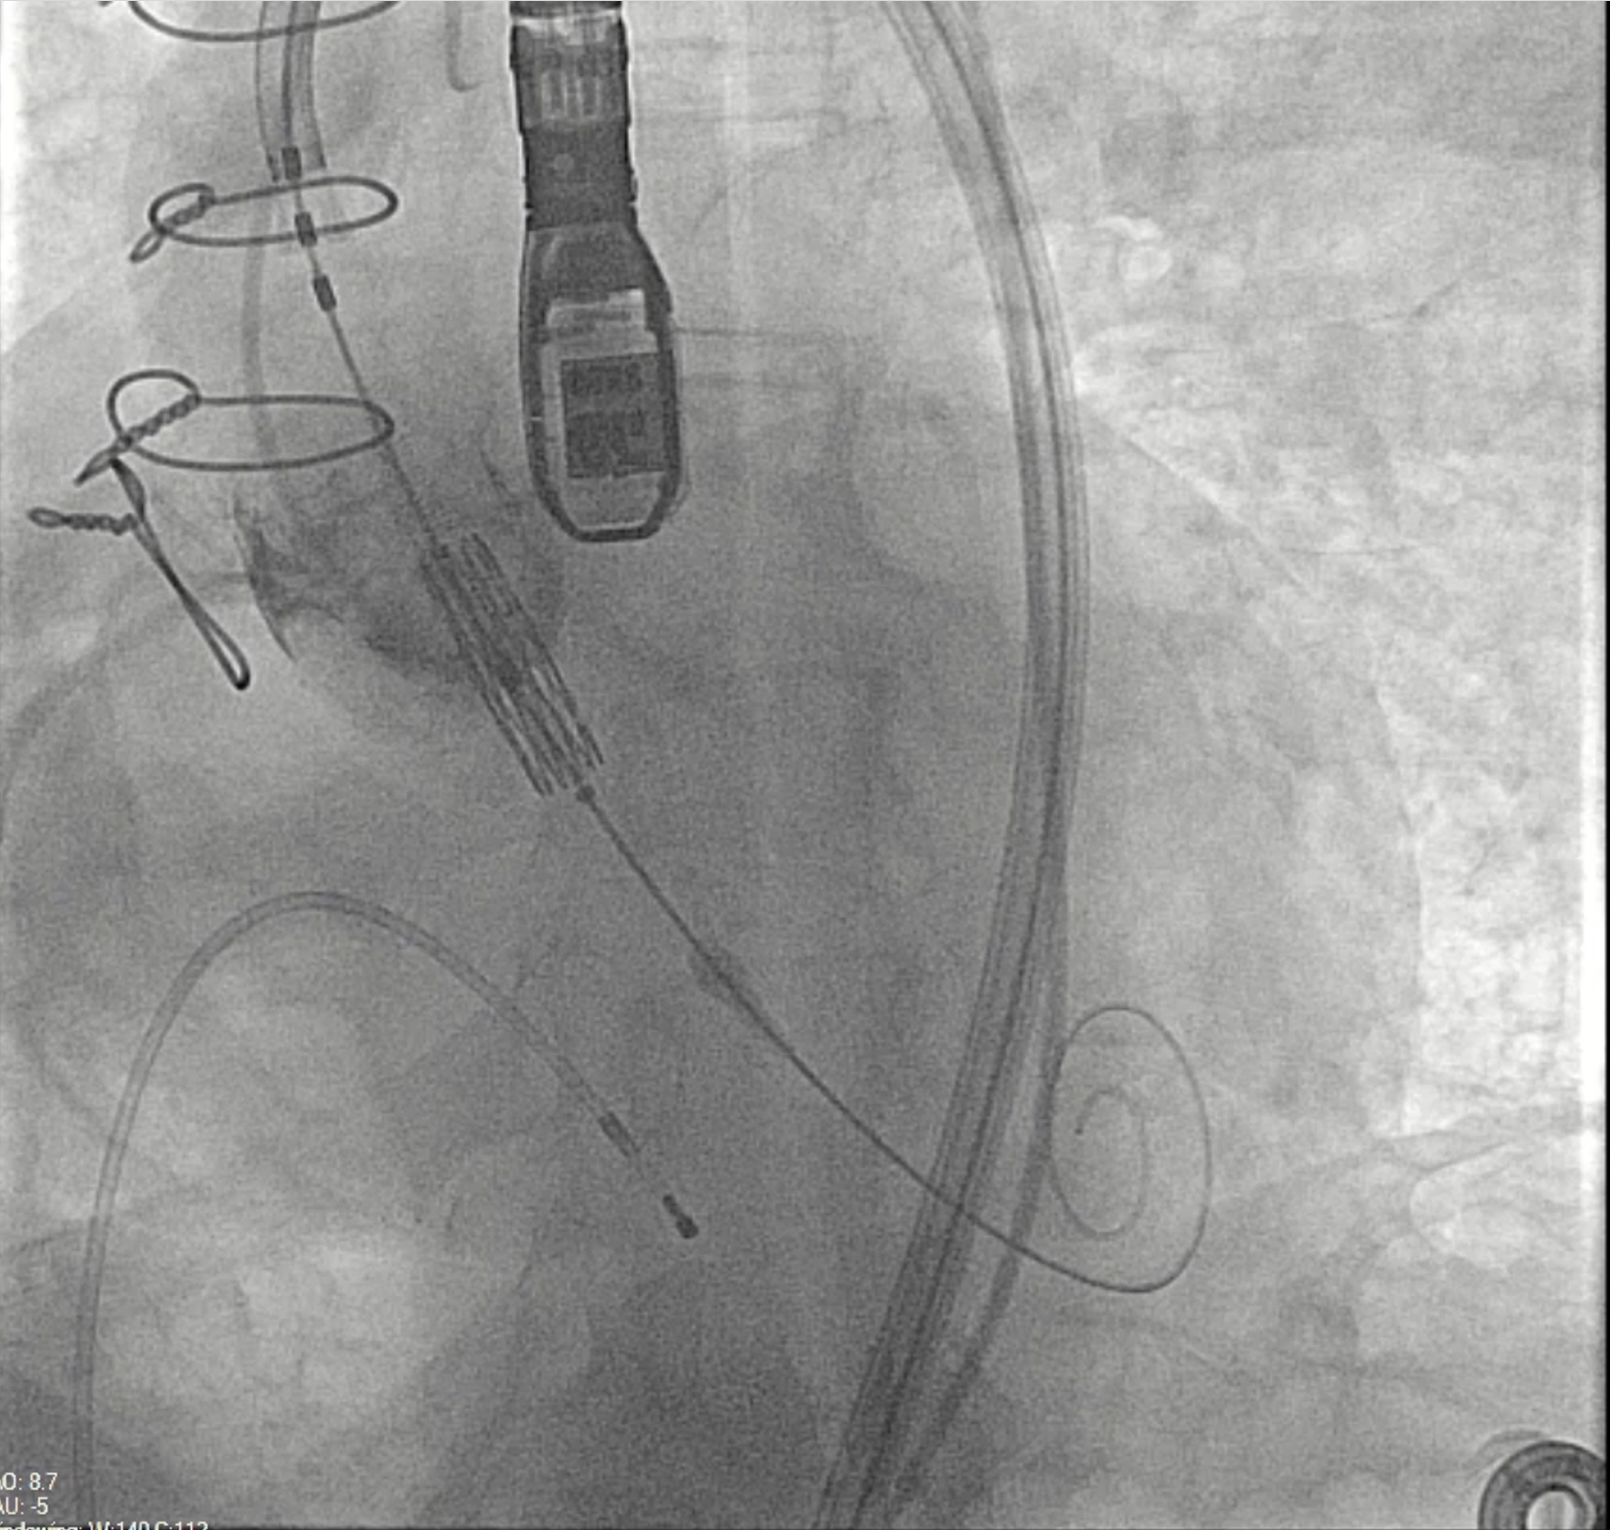

The use of stented bioprostheses facilitates THV deployment in ViV-TAVI, as most come with radiopaque markers that assist in precise placement. This benefit is diminished in stentless or homograft valves, where such markers are absent (Figure). Besides, there may be a lack of structural support for valve anchoring, particularly in cases of aortic regurgitation and no calcification.12 Data from the VIVD registry showed that stentless ViV-TAVI had a nearly doubled malposition rate and more than a double need for a second prosthesis compared with stented cases.9 Device oversizing may have played a role in malpositioning, especially given the lack of established sizing guidelines for failing stentless bioprostheses.

A balloon-expandable valve was used in 9 (60%) patients, while a self-expandable valve was deployed in the remaining 6 (40%) patients. Three high-risk patients for coronary obstruction underwent concomitant PCI with the snorkel technique to protect the coronary ostia. There were no cases of surgical conversion. However, 1 patient experienced THV malposition, requiring the deployment of a second valve; the THV migrated to the ascending aorta after post-dilatation and was snared to the ascending aorta to avoid further migration. A second THV was then placed across the previous stentless valve. During the postoperative period, this patient experienced a stroke and required the implantation of a new permanent pacemaker for a third-degree atrioventricular block. She was discharged and remains alive as of February 2025.